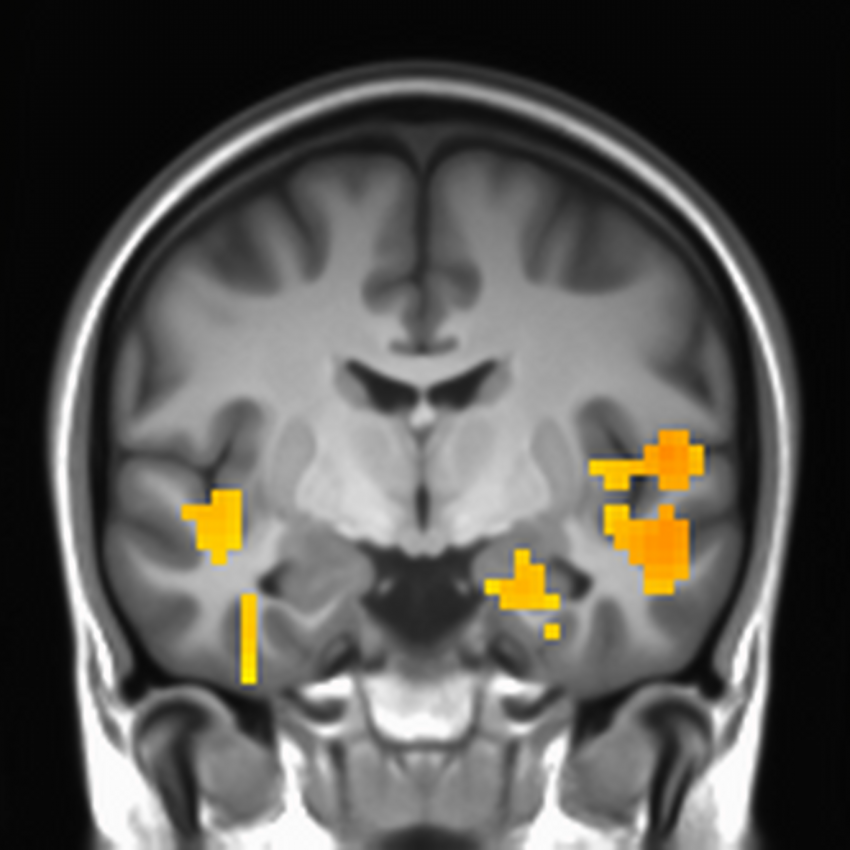

“Security professionals need to worry not only about attackers but the neurobiology of their users,” Vance said this week at the Enigma security conference in Oakland, California. His lab studied functional MRI scans of people’s brains to better understand the unconscious mechanisms that affect how they perceive often-ignored security warnings.

They noted that people tended to react hastily to a warning message or a strange email and concluded that multitasking is partly to blame for this reaction. When people encountered security warnings while in the middle of performing another task, areas in the brain connected to fully engaging with the warnings showed diminished activity. Vance’s studies also showed that people tend to be more dismissive of security warnings the second time they see them. This habituation effect could be reduced by breaking the usual rules of software design and developing security alerts that slightly change in appearance each time they pop up.